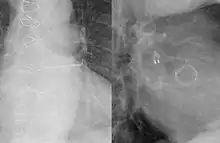

A left atrial appendage occlusion method similar to the WATCHMAN device. | |

Occlusion of the left atrial appendage can be achieved from outside the heart (the Lariat device) or from inside the heart (endovascular) with a blood-exposed implant (the Watchman and Amulet devices). The first method is a form of ligation that eliminates perfusion of the LAA. While effective in preventing many embolic strokes, it also negates the endocrine contribution (atrial natriuretic peptide) of the LAA. The second approach has many hazards as well but preserves the cardiac endocrine properties of the LAA. Further evaluation of both approaches is merited.